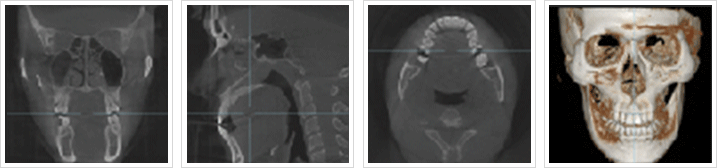

Q-ray System

메디피움만의 특별한 구강검진시스템 전문의 진단 + Q-Ray 구강검사 육안으로 확인되지 않는 숨은 충치 치태/치석 치아파절

* 스마트한 Q-Ray System - 눈으로는 확인하기 어려운 숨은 충치, 치태 등을 구강분석용 최첨단 특수장비로 촬영하는 시스템입니다.    보다 꼼꼼하고 면밀한 구강상태 분석이 가능한 스마트한 구강분석 시스템을 메디피움에서 만나보세요!